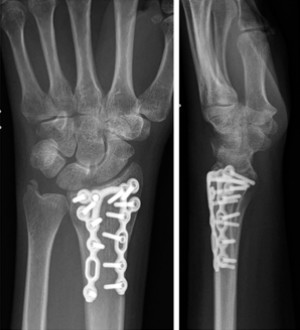

Primer ②